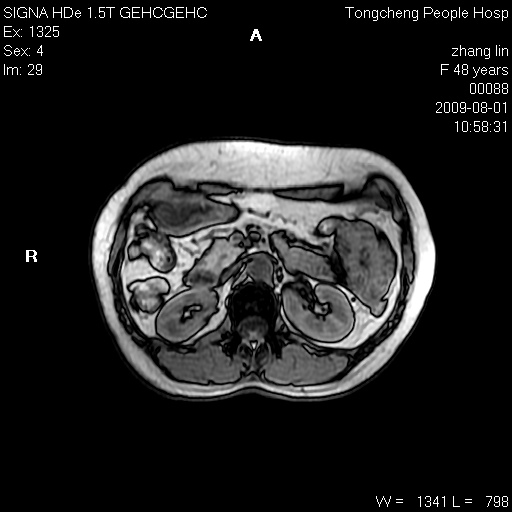

女,48岁。健康体检,彩超发现右肾占位性病变。平素健康。

临床诊断:右肾占位性病变,性质待定(囊肿?肿瘤?)。

上中腹部mr平扫+增强扫描,图像如下:

右肾上极见一类圆形病灶,t1wi呈等信号t2wi呈等高混杂信号,三期增强无强化,边界清---考虑囊肿出血。

慢性胆囊炎